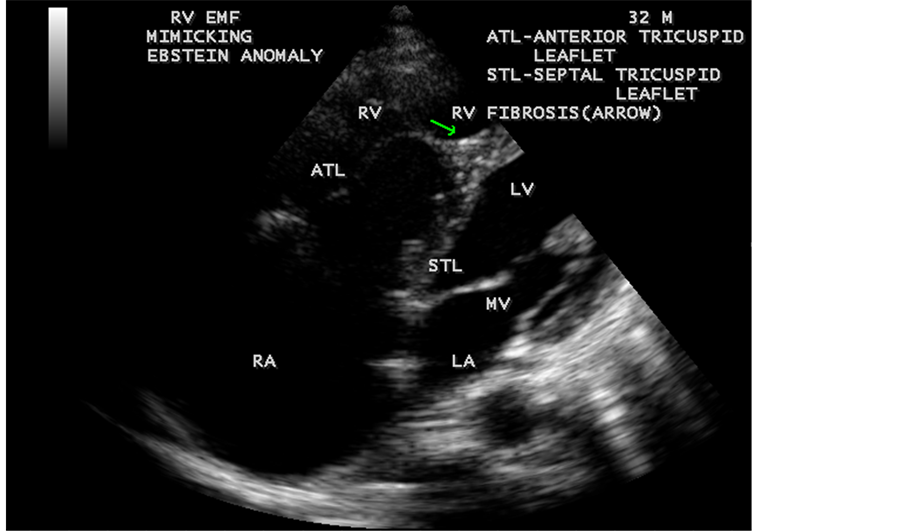

Figure 39. Right ventricular Endomyocardial fibrosis mimicking as Ebstein anomaly in a 32- year-old male. (subendocardial inflammation spreads to endocardium and results in formation of mural thrombi, which becomes organized and undergo fibrotic change, usually begins in the delicate inflow tract and involves the apex. The apical obliteration and subvalvular fibrosis reduces the size of RV cavity leading to an apparent downward displacement of tricuspid valve which is exaggerated by giant right atrium and mimic Ebstein’s anomaly).

When the endocardium is replaced by collagenous fibrosis (consists of collagen deposition and fibroblast proliferation), the final fibrotic stage is reached after several years of disease activity. Fibrotic obliteration of the apices of the affected ventricles is the hallmark of the disorder and fibrosis involving the papillary muscles and chordae tendineae leading to atrioventricular valve distortion and regurgitation. In the left ventricle, the fibrosis extends from the apex to the posterior mitral leaflet, usually sparing the anterior mitral leaflet and outflow tract and cause PML (posterior mitral leaflet) distortion and regurgitation. Like the peculiar geographical distribution, the fibrotic endomyocardial involvement stops short of the ventricular outflow tract like a ridge [17] as shown in Figure 15, Figure 29, Figure 31, Figure 35 and Figure 45. The fibrotic tissue often creates a nidus for thrombus formation, which can be extensive. Atrial thrombi also occur and the right atrium may be aneurysmally dilated. Aneurysmal right atrium with spontaneous echo contrast was detected in a 32-year-old male as shown in Figure 36 ( [18] , Figure 3]). In addition, there are fibrosis and granular septation extending into the underlying myocardial tissue and myocyte hypertrophy is common [19] . Fibrotic process causes tethering of leaflets into ventricular walls and may mimic Ebstein’s malformation as shown in Figure 39 and Figure 66 [20] [21] . Fibrosis increases the stiffness of the heart, resulting restrictive physiology, AV (atrioventricular) valve regurgitation which has been linked to atrial arrhythmias such as atrial fibrillation as shown in Figure 19 and Figure 20 in a 62-year-old female. Atrial fibrillation has been reported in more than 30% of patients with EMF. Fibrosis impairs activation patterns of the conduction system and may provide substrate for wave breaks and reentry [22] . Fibrosis reduces conduction velocity and cause conduction abnormalities like junctional rhythms, heart blocks as shown in Figure 21 and Figure 22 in a 75-year- old female and atrioventricular conduction delay [23] .

enlargement as in Figure 33 are the characteristic features of advanced stage of EMF. The fibrosed muscular trabeculae extending into the cavities from the walls of the chambers in the right ventricle visible as “cobra heads” as in Figure 4 and in pericardial sac as in Figure 29. Aneurysmal right ventricle with scattered areas of fibrosis in the sub tricuspid region and a notch in the right atrium is well seen in a 14-year-old boy as in Figure 43. Right atrial notch is frequently noticed in EMF patients as shown in Figure 42 in a 47-year-old male with left ventricular EMF and moderate pericardial effusion.